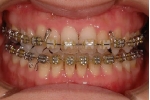

日本矯正歯科学会専門医課題症例(第7症例)

カテゴリー:開咬(overbiteがマイナスのもの)

出題基準:Overbiteがマイナスであることが必須。0mmは認めない。水平的開咬のみのケースは不可。

出題の意味:開咬とは奥歯がしっかり咬んでも(完全に閉じても)、前歯が上下的に重ならないケースを言う。Overbiteがマイナスというのは全然重なっていないということを示しており、マイナス方向に数字が大きくなるほど症状はきつくなる。つまり完全に閉じているのに、前歯の隙間から舌が見えるような状態と言うこと。この症状は、舌や唇の筋力や動かし方に原因があるので、歯を矯正するだけではだめで、舌や唇の動かし方を正常にしないと後戻りを起こしやすい。専門医の試験では、治療後2年以上経過した資料を添付して、経過が良好であることを証明しないといけないので、後戻りしやすいこのケースは難易度が高いといえる。舌や唇の動かし方をトレーニングするのは、医院スタッフ(主に筋機能訓練療法を担当する歯科衛生士)であるので、医療機関の総合力が問われる項目である。

| 治療後3年経過時

|